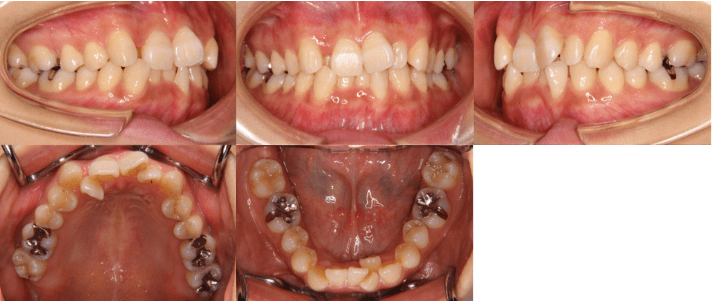

治療前

• 初診時年齢:25歳7ヶ月

• 主訴:前歯のガタガタ

• 診断:交叉咬合を伴う叢生症例

• 抜歯箇所:上顎左右4、下顎左右5

• 治療内容:小臼歯4本を抜歯した後、マウスピース型カスタムメイド矯正歯科装置(製品名インビザライン 完成物薬機法対象外)を使用して主訴である叢生の改善を行いました。

• 治療期間:2年

• リスク:矯正治療による歯の移動に伴う痛み、歯根吸収、虫歯

• 費用:88万円